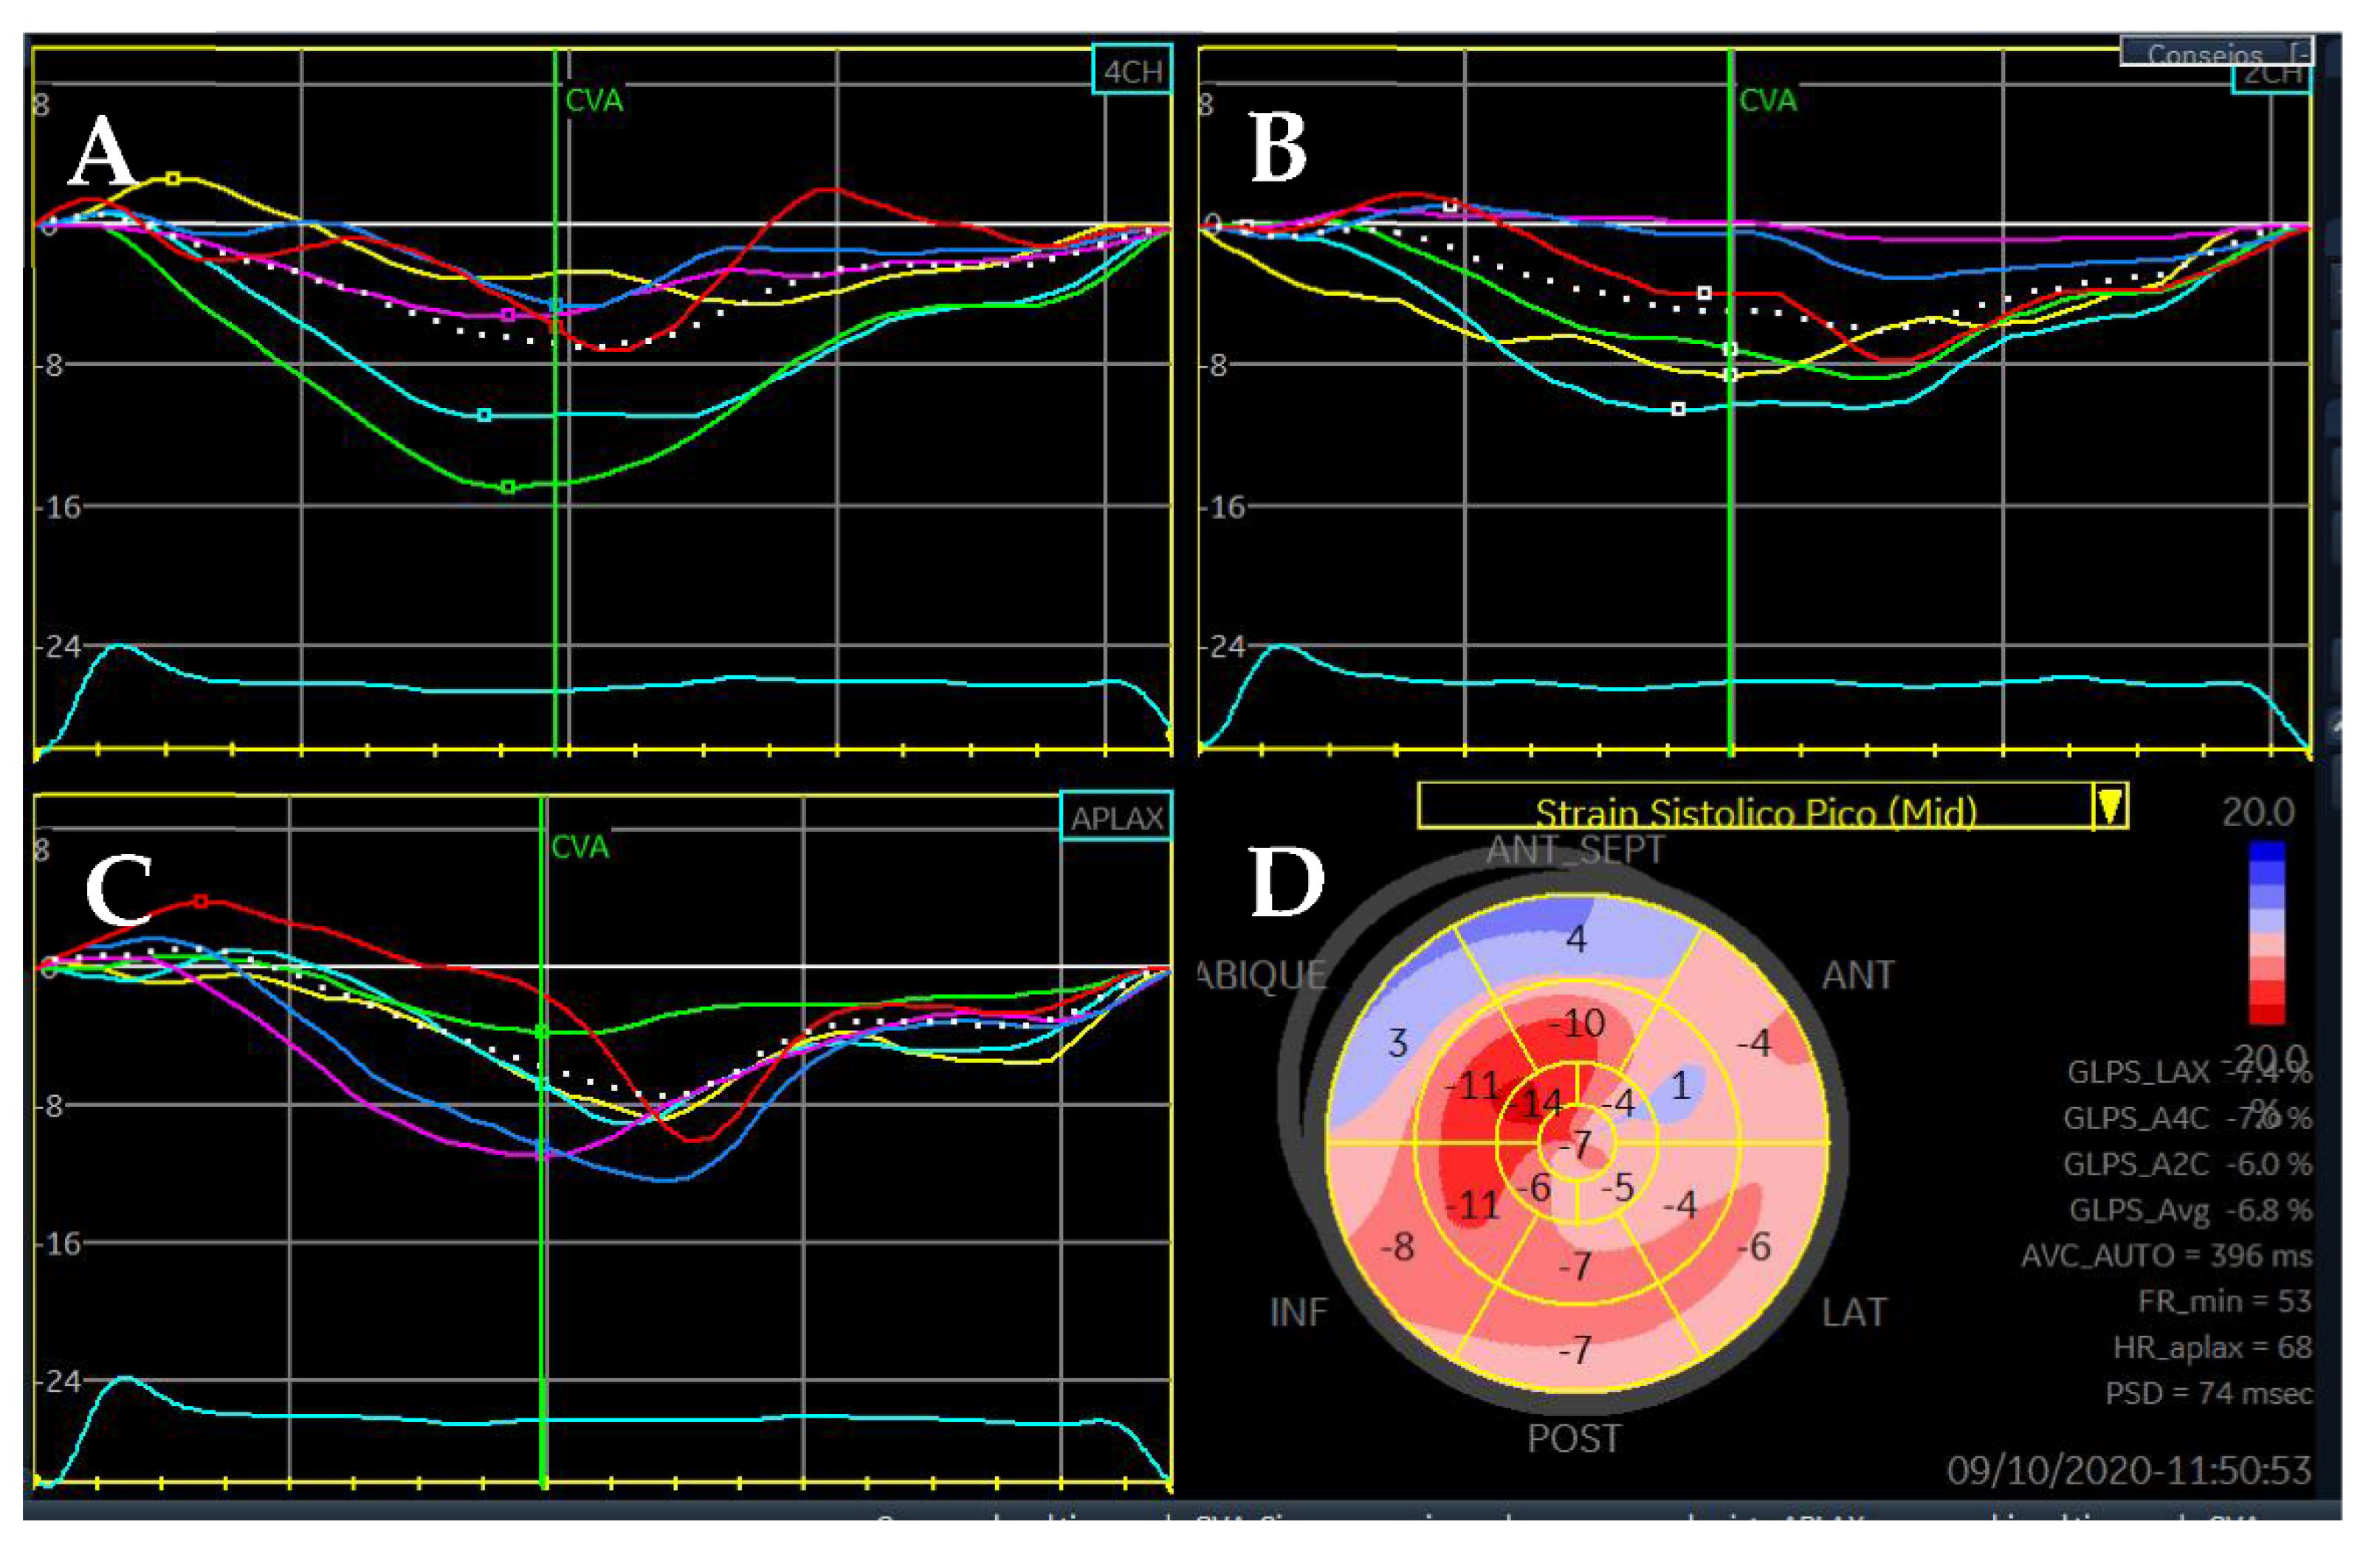

3. Dilated Cardiomyopathy